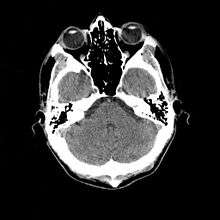

More recently, computed tomography has played a large role in reconstructing endocasts. The procedure is non-invasive and has the advantage of being able to analyze a fossil in record time with little risk of damaging the fossil under review. CT imaging is achieved through the application of x-rays to produce tomographs, or sectional density images, which are similar to the images produced during MRI scans.[8] CT scans use slices approximately 1 mm thick to reconstruct a virtual model of the specimen.[9] This method is especially useful when a fossil cranium is occupied by a natural endocast that cannot be removed without destroying the skeletal portions of the fossil. Because the cranium and its contents are of different densities, the endocranial cavity and its unique traits can be reconstructed virtually.[8]

Radiographic technique such as computed tomographic imaging, or CT scans, coupled with computer programing have been used to analyze brain endocasts from as early as 1906.[10] Recent development of advanced computer graphics technology have allowed scientists to more accurately analyze of brain endocasts. M. Vannier and G. Conroy of Washington University School of Medicine have developed a system that images and analyzes surface morphologies in 3D. Scientists are able to encode surface landmarks that allows them to analyze sulcal length, cortical asymmetries and volume.[11] Radiologist, paleoanthropologists, computer scientists in both the United States and Europe have collaborated to study such fossils using virtual techniques.[10]